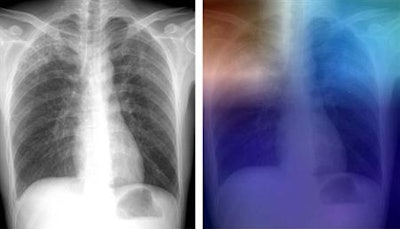

Artificial intelligence (AI) software can accurately identify tuberculosis (TB) on chest radiographs, offering the potential to serve as an inexpensive or even free method to screen for the often deadly disease in underserved countries, according to a study published online April 25 in Radiology.

To train the neural networks to learn to how to detect TB, the researchers used 685 posteroanterior chest radiographs that were assembled from four sources of data: two publicly available datasets from the U.S. National Institutes of Health (NIH), a dataset from Thomas Jefferson University, and a dataset from the Belarus Tuberculosis Portal.